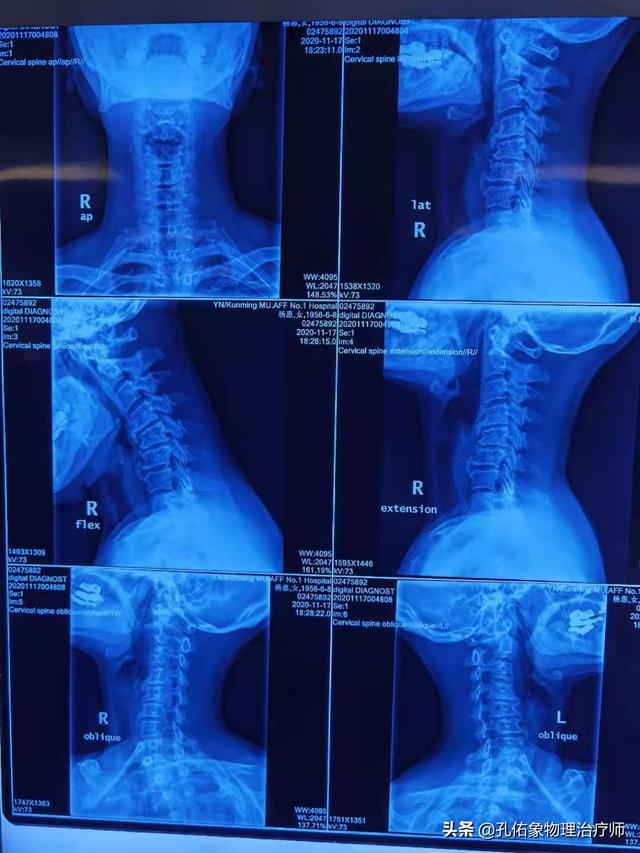

1. apparition précoce : il y aEn cas de douleur aiguë, il peut être conseillé au patient de passer une radiographie du cou.L'objectif est d'améliorer la mobilité des articulations douloureuses de la colonne vertébrale cervicale.

Le problème de l'épaule gelée nécessite une meilleure prise en compte de la colonne cervicale dans le processus de diagnostic et de traitement. Si la douleur est causée par un problème au niveau de la colonne cervicale et un nerf pincé, on pense qu'il est impossible de la guérir.